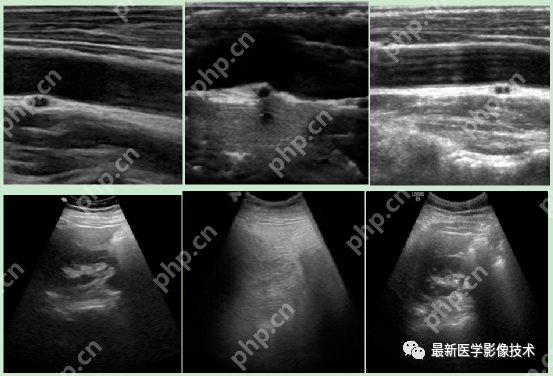

5、验证集部分生成结果

左图为低质量图像,中间为生成的高质量图像,右图为真实的高质量图像。